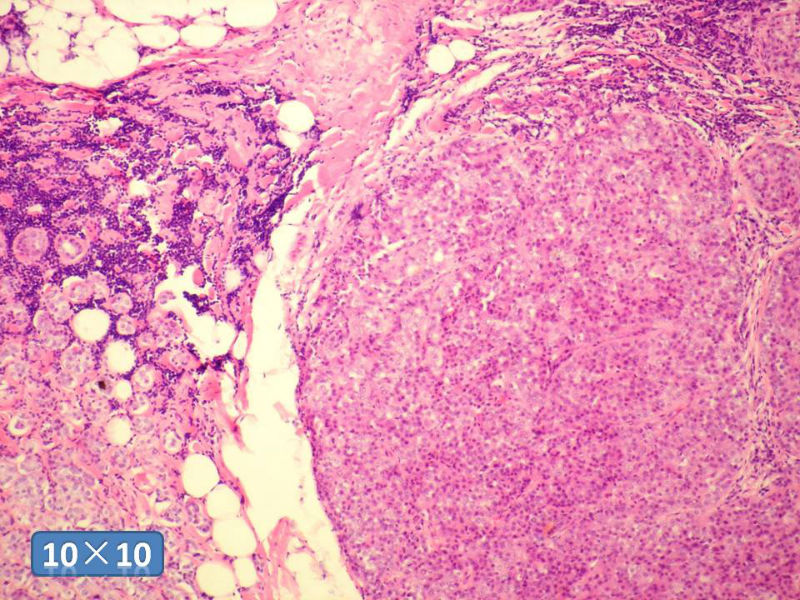

女性,50岁,乳腺肿物,冰冻切片(图1-25)

HE